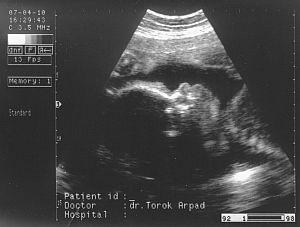

Ez a kis arca, szembööl. Kép

Ez az elsöö kukis képe 27. hetesen :-)

Kép

Második kukis kép 29 hetesen :-) Kép

ès itt van öö, profilbol. Kép

Nagyon utálta az uh-t, a kis keze ott van az arcocskája elöött. Remélem, hogy minden kivehetöö.

Kata: Nagyon édi!! A 29 hetest nem tom kivenni :oops:

Ott rajta van az egész lábacskája, ahogy kicsit összehúzza és jobb oldalt, a combjánál látszanak a kis heréi. :D